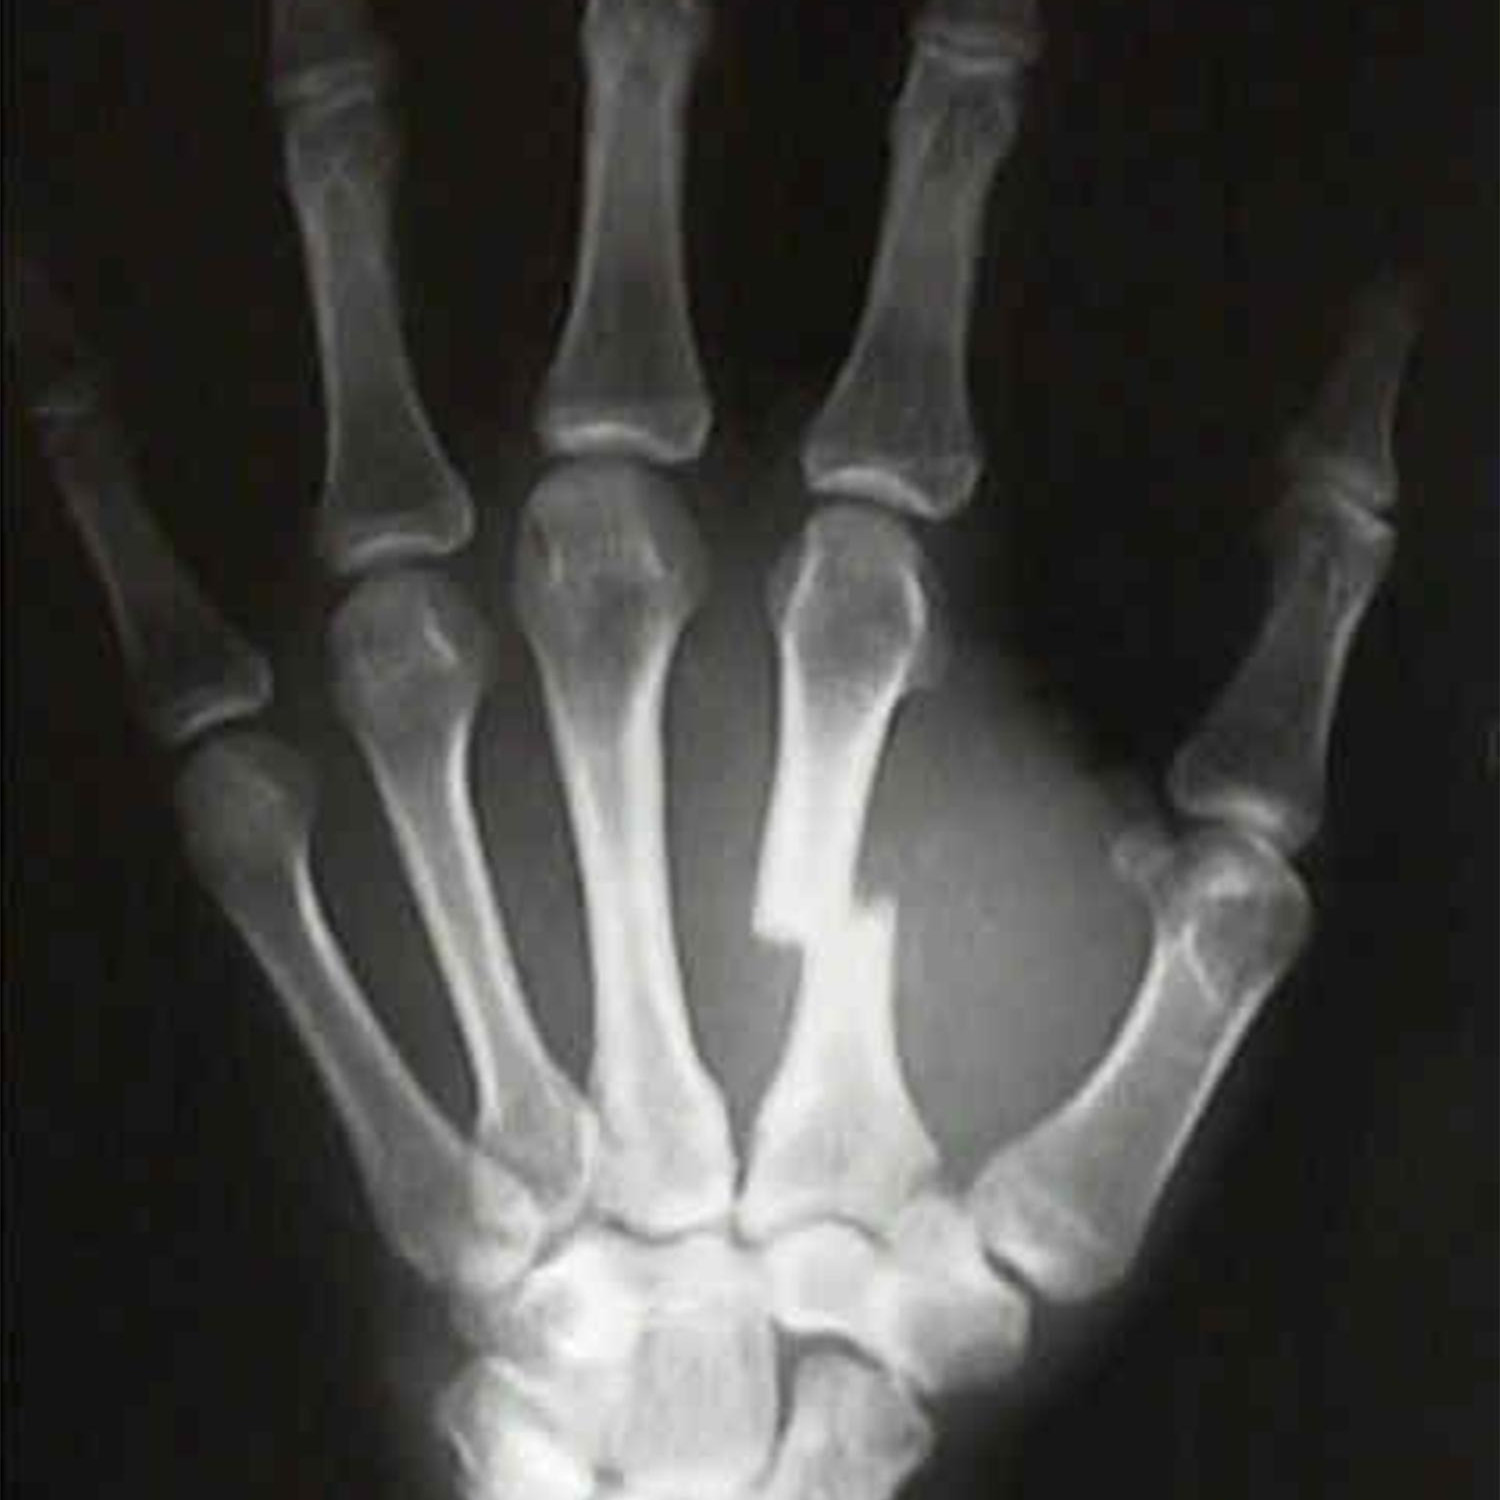

• Вы знаете, как исправить перелом пястной кости?

Вы знаете, как исправить перелом пястной кости?

Перелом пястно-фаланговых костей является частым переломом при травме кисти, на долю которого приходится около 1/4 пациентов с травмой кисти.Из-за деликатной и сложной структуры кисти и тонкой моторики лечение переломов кисти является гораздо более важным и технически сложным, чем лечение других длинных трубчатых переломов.